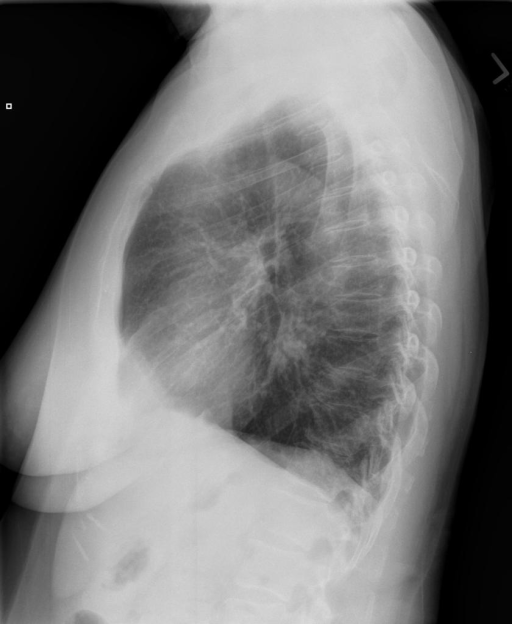

In conventional chest X-Ray exams, the erect patient is positioned between an X-Ray tube and a detector. The collected data by the detector is then used to create a comprehensive image. The main distinctions in positioning (such as anteroposterior (AP) and posteroanterior (PA), both of which we refer to a Frontal, or lateral (L)), are related to which view enables the most insight.

We compare our projected X-Rays with samples from the OpenI dataset for frontal and lateral views in Figure 5. The differences in the frontal view are due to the different positioning of the shoulder girdle. In the X-Rays, the arms are usually placed alongside the body, while in the projected images, the arms are raised due to the nature of the CT scan. In the lateral view, the X-Rays show a more comprehensive range of orientation and pose. However, the projected images, typically taken while the patient is lying down, result in similar poses between the different images. This leads to visual differences between images of female patients in both frontal and lateral views, such as the third column and second row of real X-Ray images and the first column and second row of projected images.